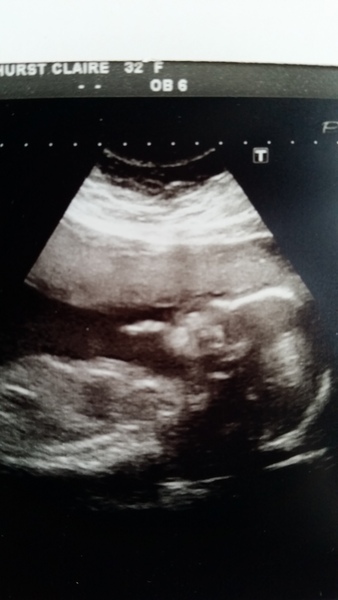

Loving all the lovely scan news.

.. My growth scan is on Monday. Can't wait.